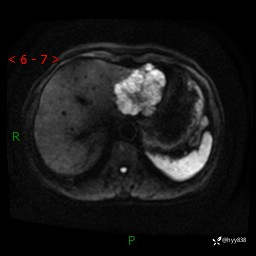

老年女性,偶然发现肝脏占位,综合各个序列,你考虑什么---结果公布

主诉:发现肝脏占位性病变2天

简要病史:患者2天前因“腰疼”至当地医院就诊时发现肝脏左叶占位性病变,无发热、畏寒,无皮肤黄染,无腹痛、腹泻,无恶心、呕吐、厌油等不适,今进一步诊治遂来我院就诊,门诊以“肝脏占位性病变性质待查”收入我科。 起病以来,患者精神、睡眠一般,饮食欠佳,二便正常,体力、体重无明显减轻,

辅助检查:MRI

临床诊断:肝占位

肝脏MRI平扫(同反相位)

T2WIfs+DWI

增强(动脉期+静脉期+延迟期)